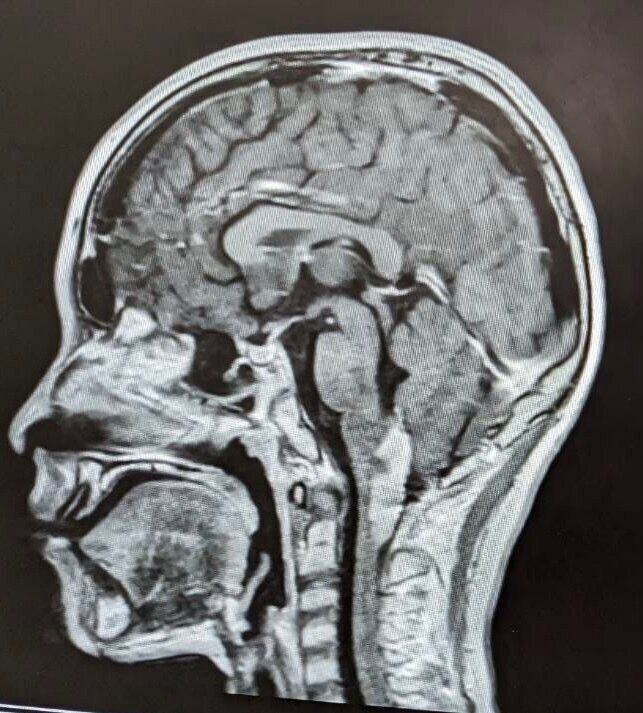

脳幹グリオーマとは、脳幹に発生する脳腫瘍です。脳幹は、大脳を支える幹のような形をした部分で、呼吸をする、心臓を動かすなど、生きていくために欠かせない働きをコントロ―ルする、とても重要な部位です。

「このときの説明も詳しいことは覚えていないんですが、腫瘍が延髄(えんずい)から頚髄(けいずい)に縦にできていて、発生場所としてはレアケースだ、という説明を受けたと思います。小児がんの中でも小児脳腫瘍の症例は少なく、さらに、海智の腫瘍は今まで見たことない場所にあると。

そして、『脳幹部に重要な機能障害が起こるリスクが高いので、摘出手術はできません。また、海智くんの腫瘍のケースは、放射線治療や化学療法(抗がん剤治療)はあまり効果が期待できません』と言われました」(恭平さん)